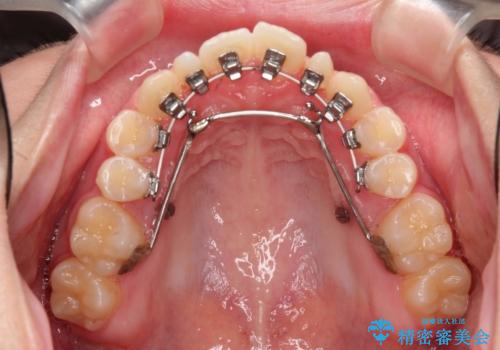

オールセラミッククラウン 再根管治療後の補綴

- 他院にて右下4番目の歯の再根管治療が必要だと言われた方の症例です。

再根管治療終了後、オールセラミッククラウンによる補綴を行いました。

今回用いたオールセラミッククラウンは、ジルコニアフレームという白い素材の上にセラミックを盛っているため審美性が非常に高いのが特徴です。

またジルコニアは人工ダイヤモンドの材料にも使われているほど高い強度を持っており、そのためオールセラミッククラウンは審美性だけでなく、奥歯やブリッジの補綴も可能とするクラウンです。